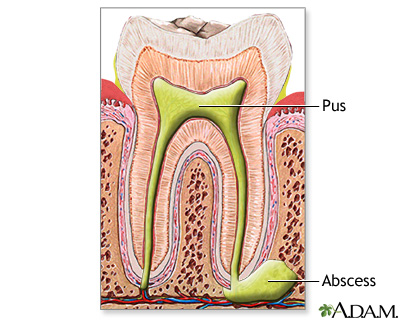

- Tooth abscess

Abscesses can form in almost any part of the body. The skin, under the skin, and around the teeth are the most common sites. Abscesses may be caused by bacteria, parasites, and foreign substances.

Abscesses in the skin are easy to see. They are red, raised, and painful. Abscesses in other areas of the body may not be seen, but they may cause organ damage.

Preventing abscesses depends on where they develop. For example, good hygiene can help prevent skin abscesses. Dental hygiene and routine care will prevent tooth abscesses.